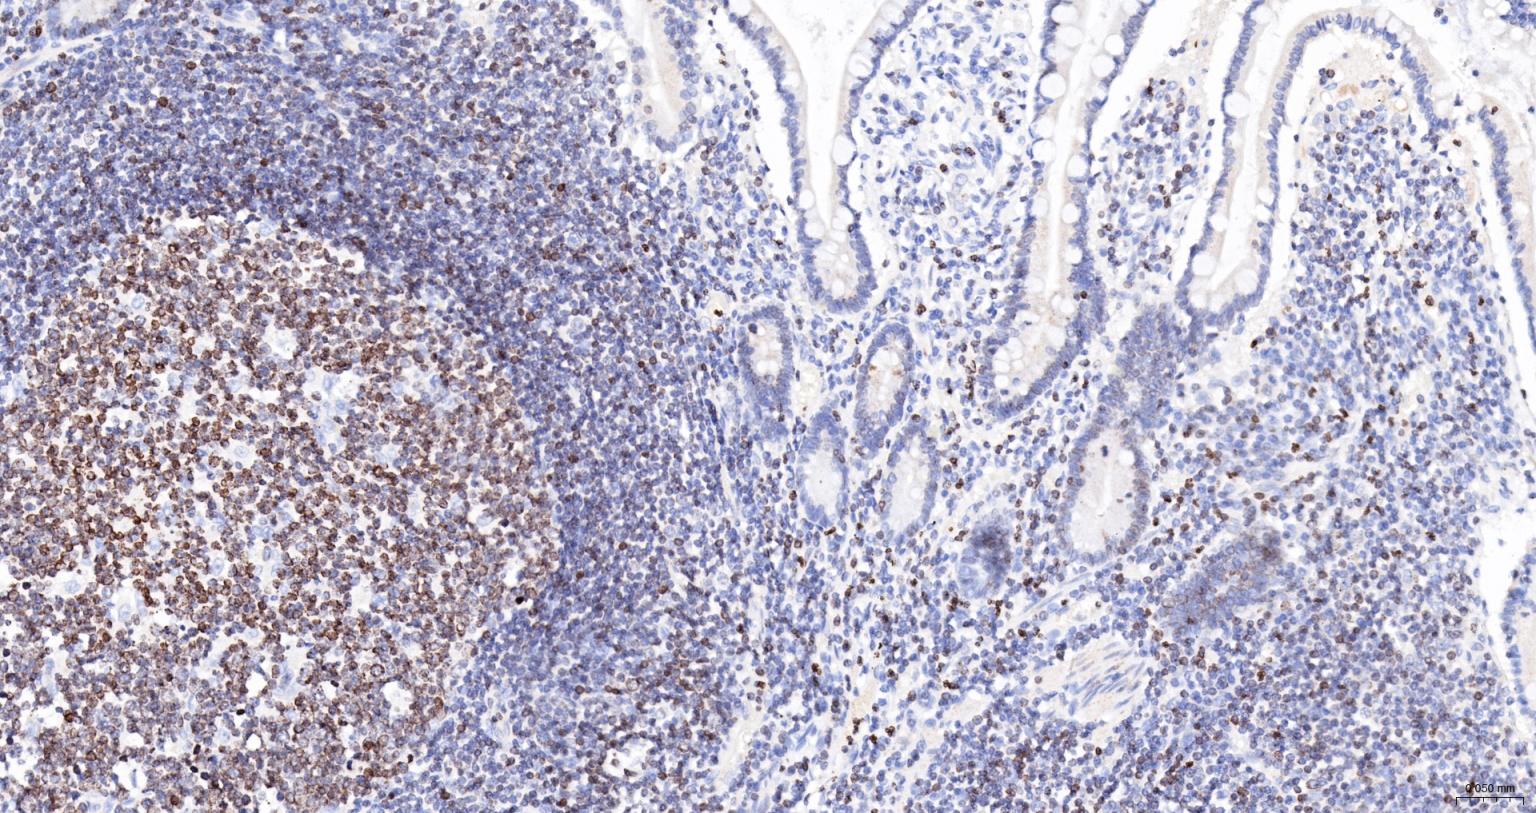

Paraformaldehyde-fixed, paraffin embedded Human Small Intestine; Antigen retrieval by boiling in sodium citrate buffer (pH6.0) for 15 min; The section was incubated with Lamin B Receptor Monoclonal Antibody, Unconjugated (bsm-61224R) at 1:200 overnight at 4°C, followed by conjugation to the bs-0295G-HRP and DAB (C-0010) staining.